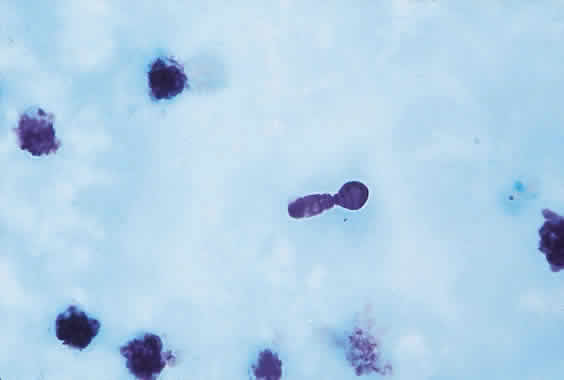

Yeasts or yeastlike fungi (e.g., C. albicans) are single-cell organisms, typically round or oval, that form discrete, smooth, creamy and moist colonies (Fig. 1) within 24 to 72 hours on routine microbiologic media. They reproduce or multiply by budding. The characteristic appearance is shown in Figures 2 and 3. Molds (e.g., Aspergillus fumigatus) are multicellular fungi that contain tubular structures (hyphae) and grow by branching and longitudinal extension. These are identified by their macroscopic (Fig. 4) appearance (e.g., cottony, woolly, powdery) or microscopic structures (conidia, hyphal segmentation), and color (Fig. 5). Some fungi may grow with both yeastlike and hyphal morphology in tissues or culture.

Fig. 2. Candida albicans on Giemsa stain showing budding.